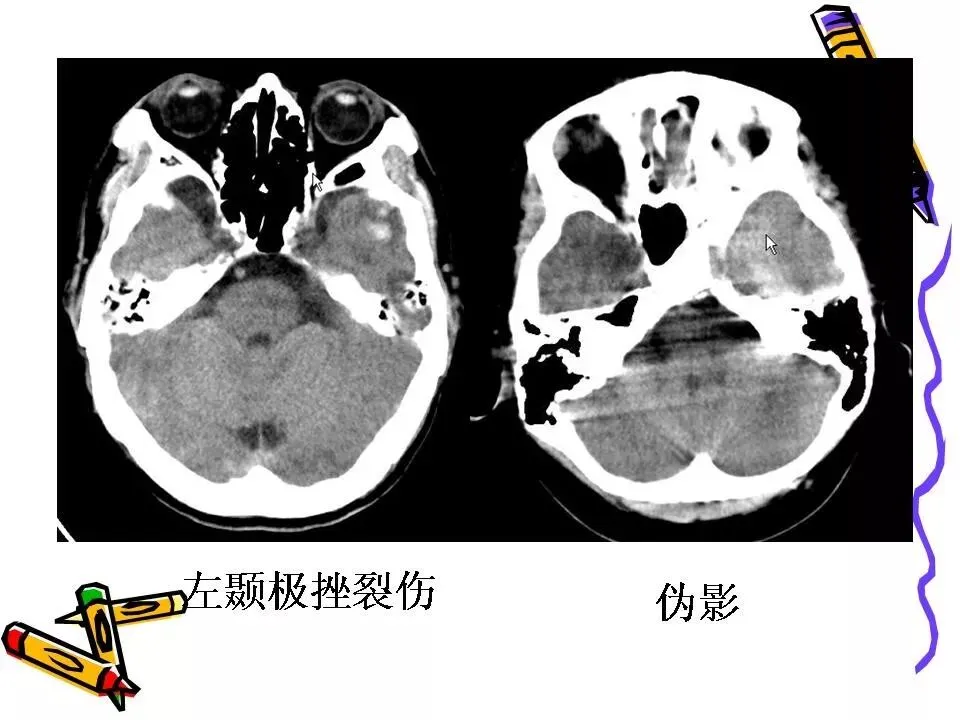

>常见颅脑外伤CT诊断(PPT)

常见颅脑外伤CT诊断(PPT)